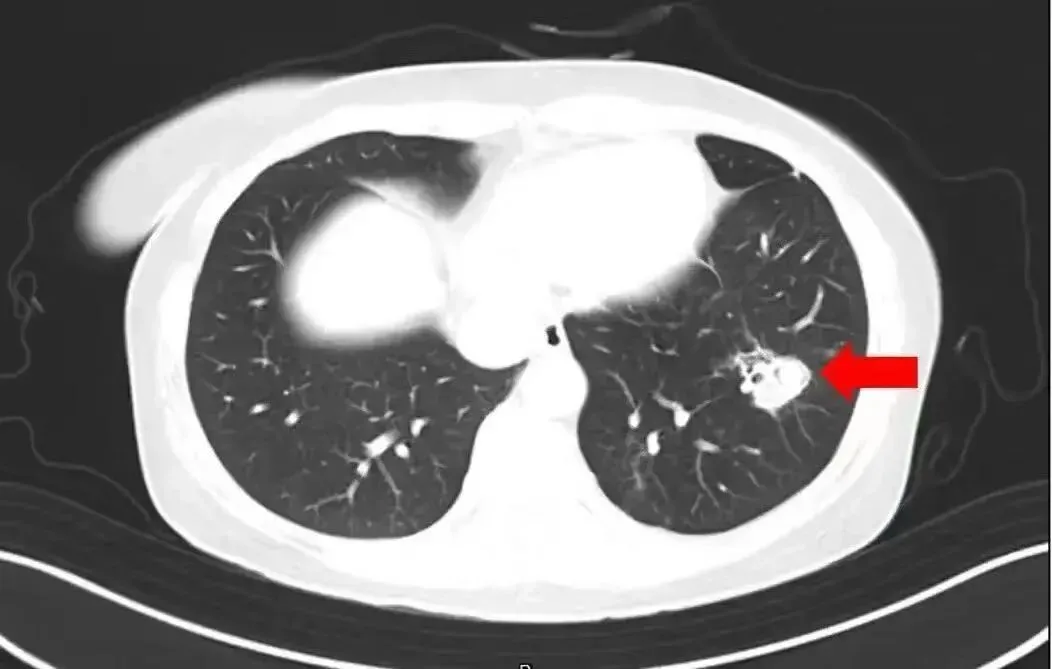

北京佑安医院感染综合科主任医师李侗曾介绍,对于免疫力低下的人,吸入了这些真菌,就会发病引起肺部的病变——曲霉肺炎。因为它是通过呼吸道感染的,进入血液后可以扩散到全身。大脑因为血供最丰富,所以也是真菌最容易侵犯的器官。

烟曲霉等特定霉菌,对免疫力较弱的人,还可能带来致命的肺部感染。烟曲霉被世界卫生组织列入首份真菌“重点病原体”清单,侵袭性曲霉菌病一旦发生就是危重症。腐烂的落叶上很可能就附着了烟曲霉。